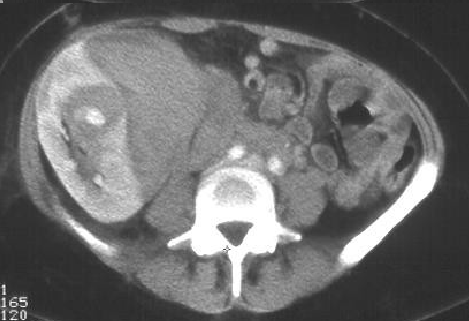

肾外出血或肾包膜下出血有时会偶然发现在随访的病例,CT最常表现为包膜下的血肿,罕有危及生命的大出血。 病例1 女性,32岁,肾移植后 常规活检

假性动脉瘤 肾包膜下血肿通常与损伤的动脉交通。动脉瘤与肾盂肾盏交通导致间歇性血尿